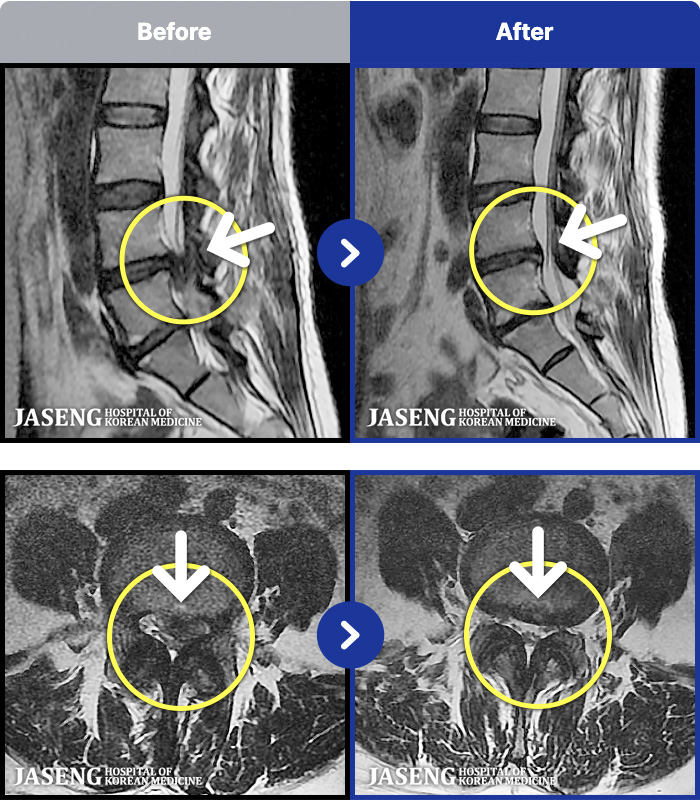

MRI ġ

MRI ũ ʸ Ȯϼ.